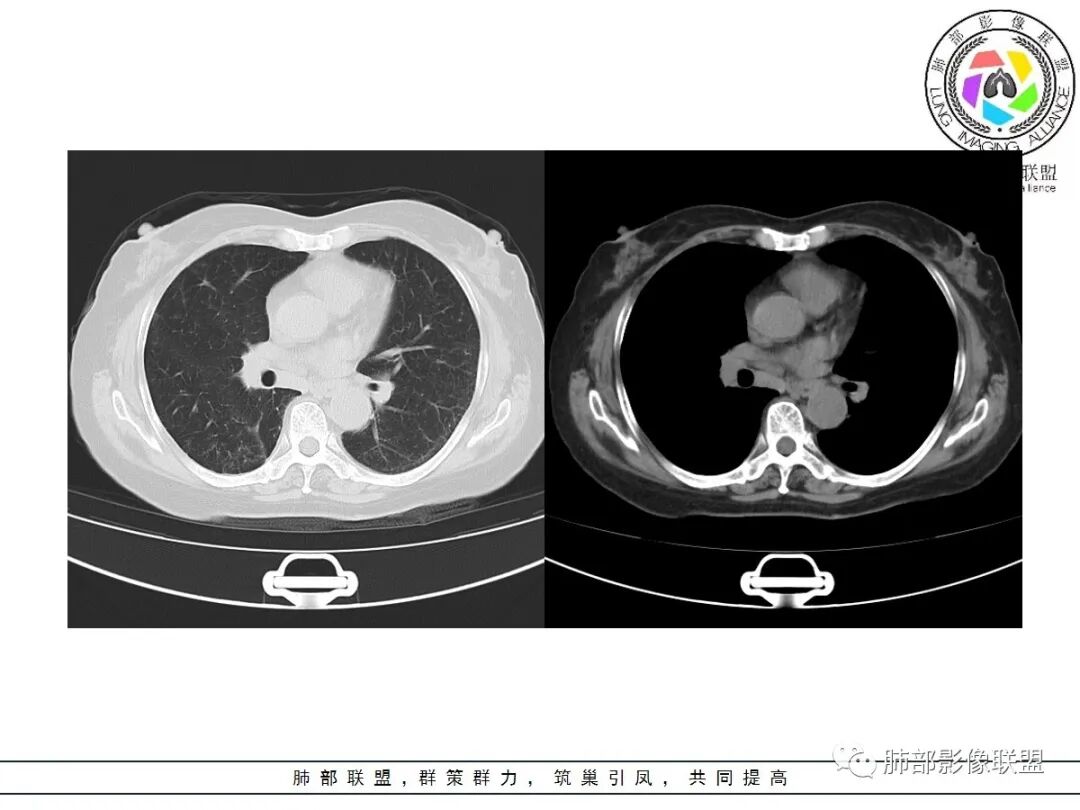

老年女性,咳嗽、咳痰气短9月余,胸部CT提示右下肺可见一斑片状密度增高影,宽基底与胸膜相连,内有散在透亮区,空泡,支气管走形礓直,周边可见散在结节影,不均匀强化,冠状位可见胸膜牵拉,考虑腺癌可能,鉴别结核;

老年女性,咳嗽咳痰,气促九月余,抗感染治疗症状稍改善,胸部CT示病灶稍缩小。右肺下叶可见大片实变影,宽基底与胸膜相连,内部支气管扩张,周边散在小结节影,增强扫描部分区域明显强化,病灶边缘可见血管影,冠状位叶间裂可见胸膜牵拉,综合考虑为恶性病变,肺炎性肺癌,鉴别结核,淋巴瘤;

这个病灶的特点包括:右下叶整体体积缩小,局部病灶是占位效应——明显膨隆,边缘是膨隆加收缩并存;病灶边缘磨玻璃影边界清楚;内部除了含气的支气管之外,还有一些小空泡样的蜂窝肺,并有残留的肺组织;附近结节里面有小空泡,和大病灶是一致的。整个胸膜跟斜裂与病灶有牵拉、凹陷、有收缩力;增强不是很明显,强化不均匀。实变在外围,长轴与胸膜平行。支气管进入到病灶里走行整体通畅,但是有些远端有些堵塞,我们通过后面增强可以看清。综合分析整个病灶还是符合肺炎型肺癌的特点。还有一点,上肺有个小钙化灶索条状影——考虑陈旧性肺结核。